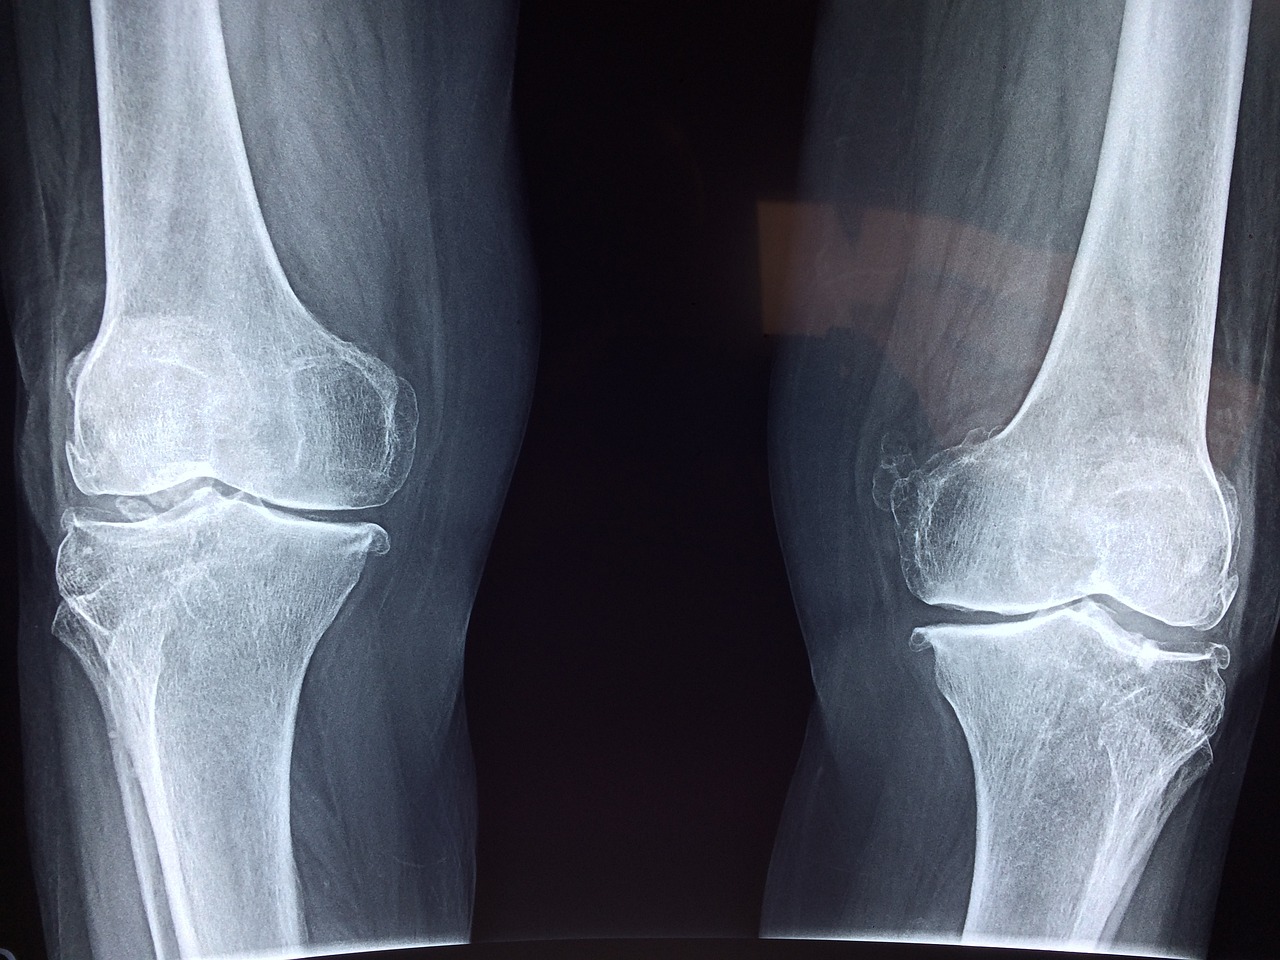

관절염은 관절의 염증으로 인해 발생하는 질환으로, 다양한 유형과 원인이 있습니다. 관절염은 전 세계적으로 수백만 명에게 영향을 미치며, 통증과 불편함을 유발하여 삶의 질을 저하시킬 수 있습니다. 대표적인 관절염의 유형은 골관절염(Osteoarthritis)과 류마티스 관절염(Rheumatoid Arthritis)입니다.

- 골관절염(Osteoarthritis): 연골이 점차적으로 닳아 없어지는 퇴행성 질환으로, 주로 노화나 반복적인 사용으로 인해 발생합니다. 무릎, 엉덩이, 손가락 관절에 주로 발생합니다.